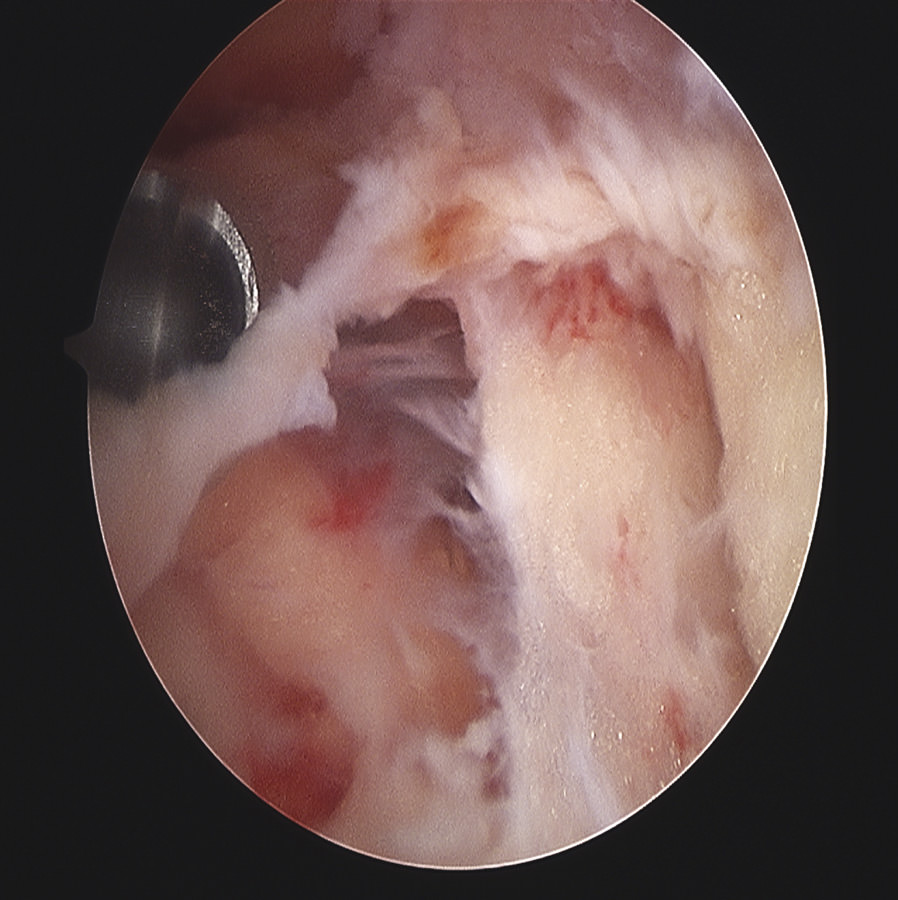

Siguiendo por los recesos lateral y medial (Figura 5) se llega a la zona suprapatelar, cuya fibrosis es la primera causa de limitación de la flexión (Figura 6). En este espacio hay que ser muy meticuloso para resecar con motor (Figura 7) y radiofrecuencia las adherencias, los nódulos, cíclopes (Figura 8), la fascia profunda del cuádriceps, con esqueletización de la cara anterior de fémur si es necesario, y liberar el alerón externo e interno, en función de la rótula: si está lateralizada (liberación solo lateral) o bien centrada (liberación lateral y medial), para facilitar el recorrido rotuliano. La limpieza de este espacio es fundamental para recuperar el máximo grado de flexión.

Figura 6. Bandas fibrosas articulares con disfunción patelofemoral y dolor anterior en prótesis de rodilla.